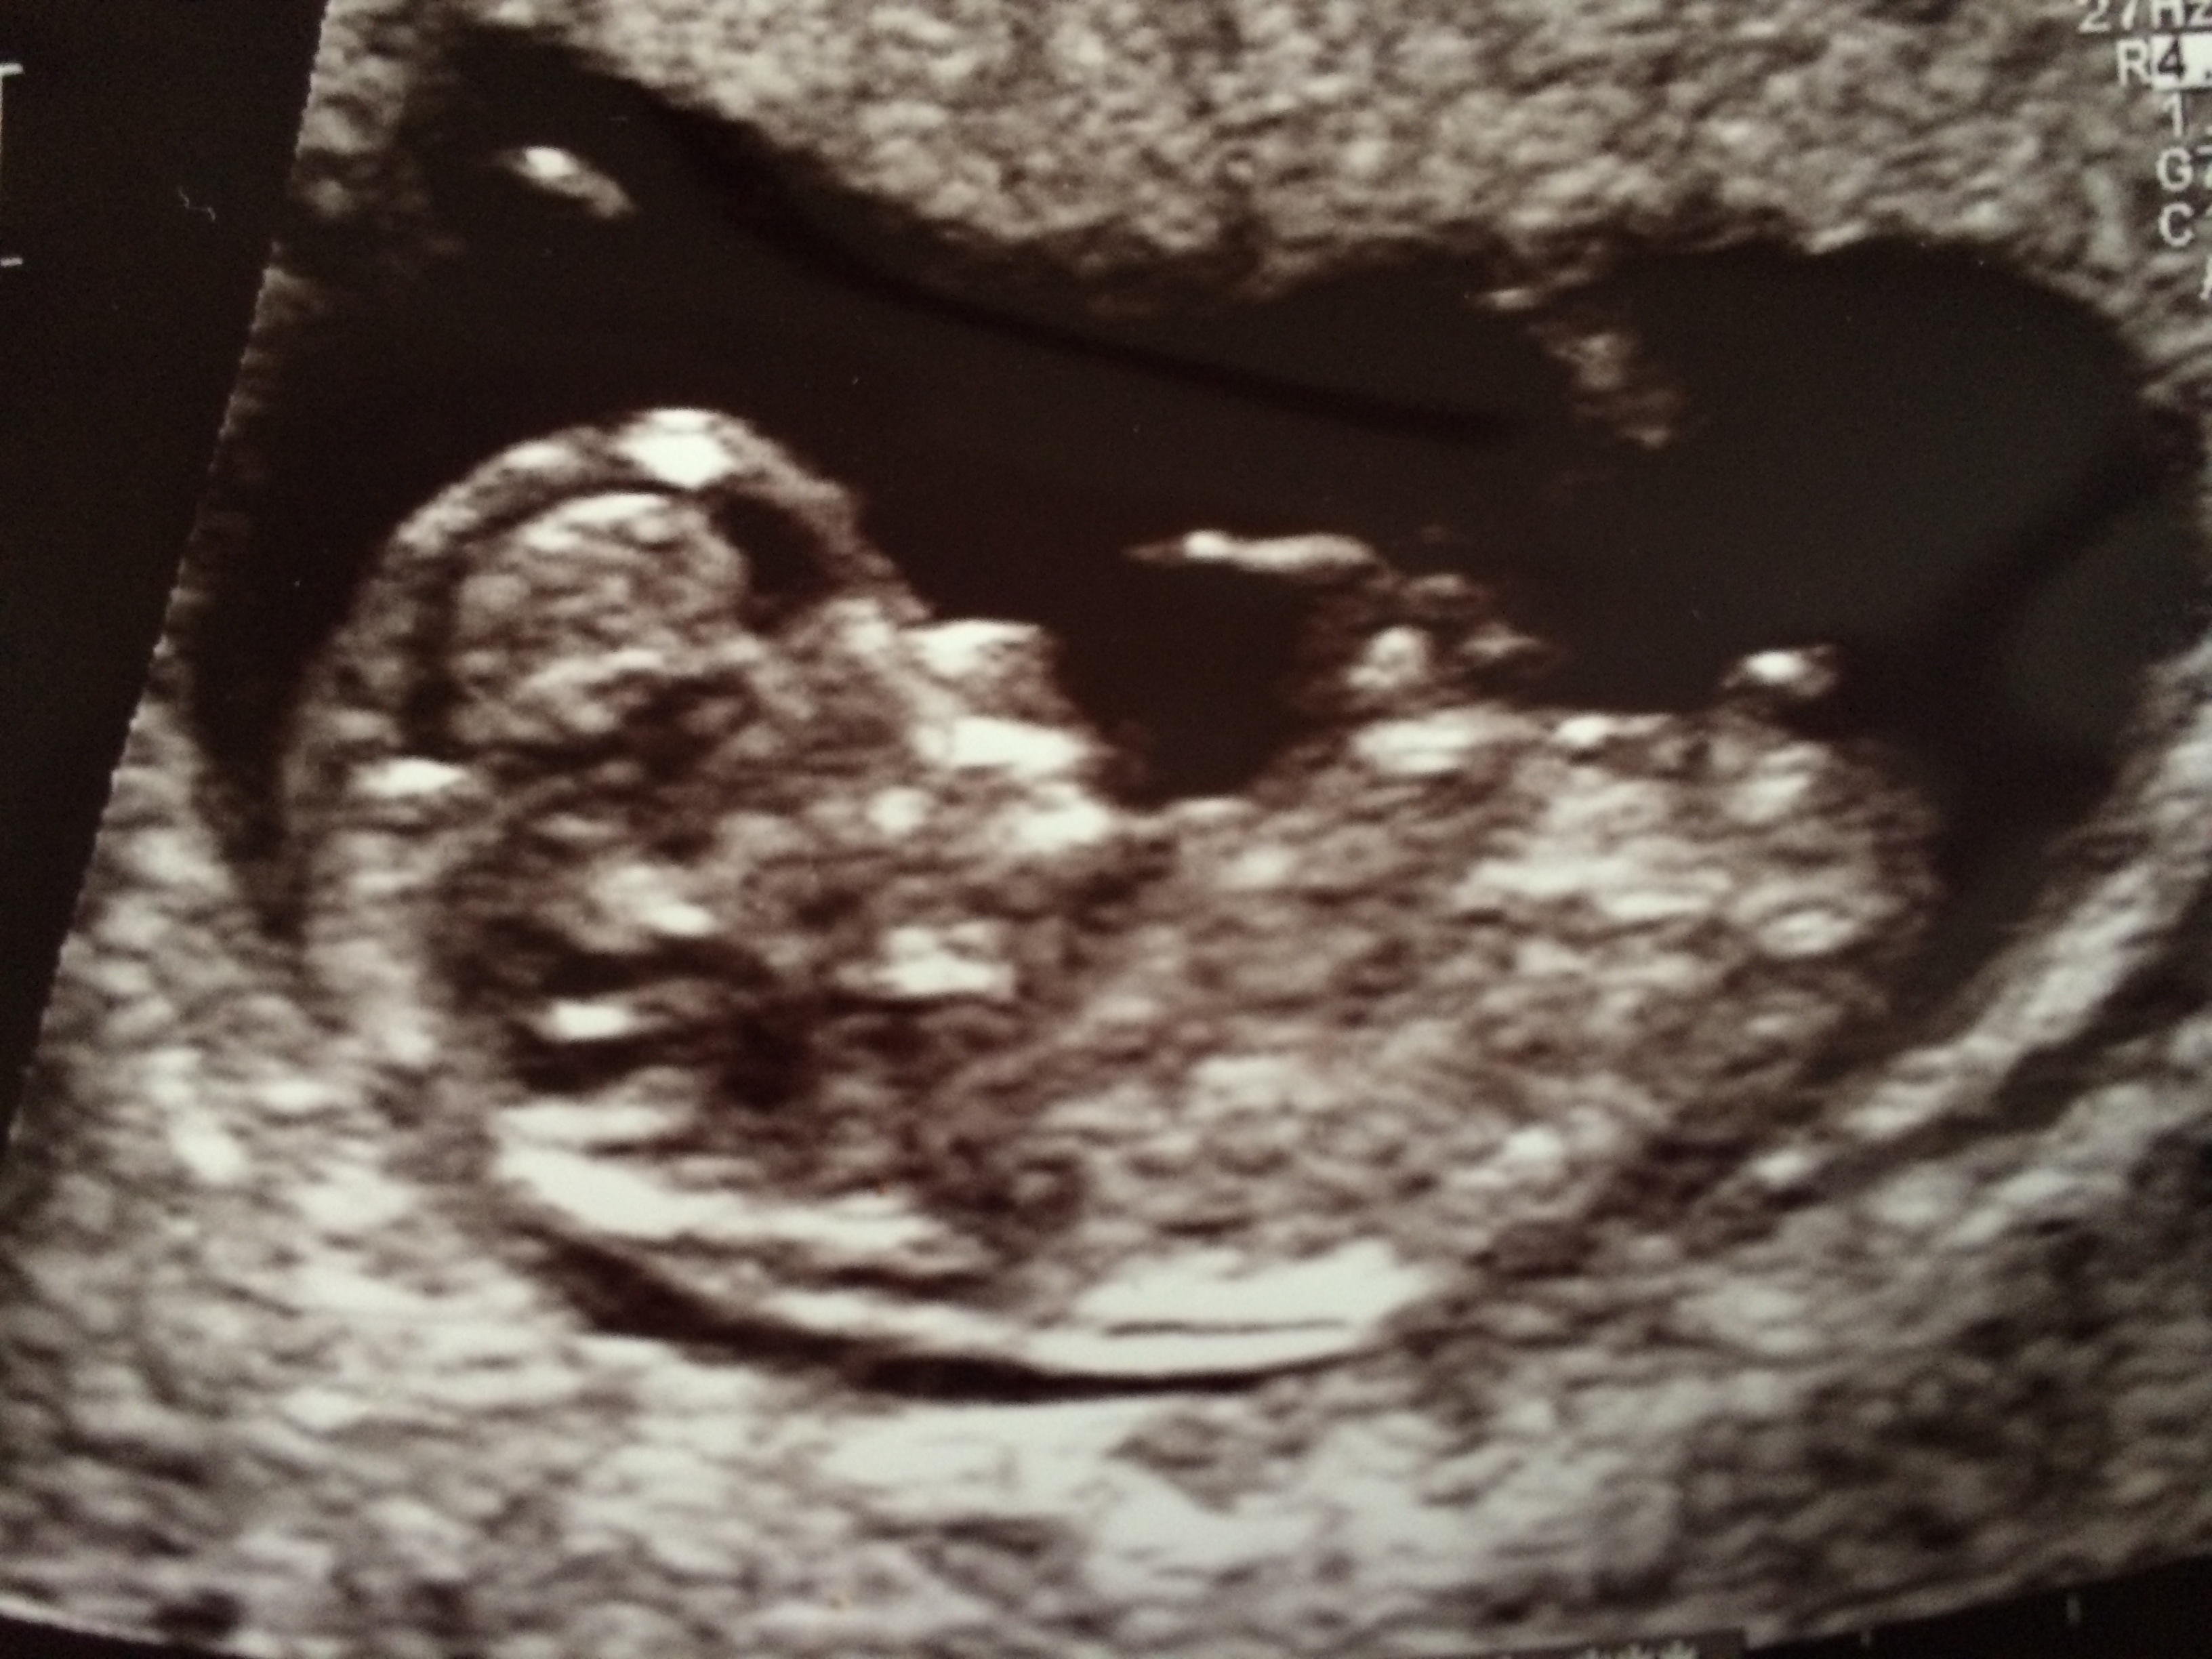

This is my 11 weeks scan (too early for nub I guess?). What do you think (skull theory), boy or girl?Attachment 17662

Hmm... although it is a little early I think I'm leaning boy (75%) - congrats x

Too early to tell sorry xx

Lookalike a boy but too early.

I agree....too early but it does look like a little boy nub starting to form :)

It's 50/50 in the 11th weeks, before the 12 week the nub is pretty much the same.